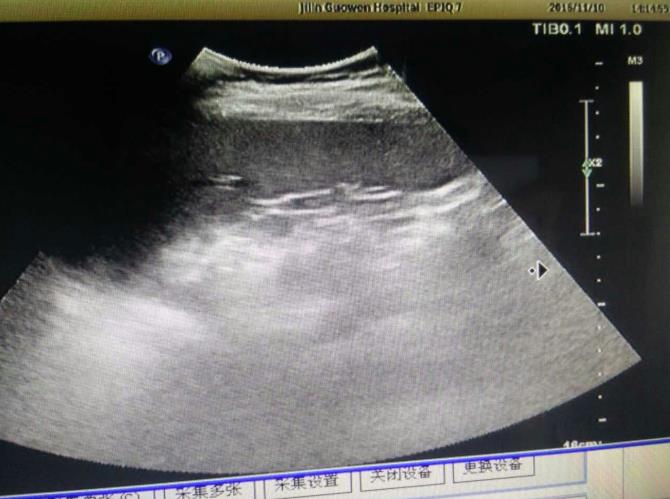

為該患常規(guī)檢查臍帶入口時發(fā)現(xiàn)臍帶入口位于胎盤下緣邊緣,胎兒超聲檢查無陽性發(fā)現(xiàn)。常規(guī)掃查右卵巢時,發(fā)現(xiàn)右卵巢旁可見腎臟回聲(正常情況下,右卵巢旁是不會掃查到腎臟回聲的),大小、形態(tài)如常,CDFI:腎內(nèi)血流灌注尚可,故囑患者左側(cè)臥位,顯示孕婦右腎位置、大小及形態(tài)正常,囑孕婦右側(cè)臥位,發(fā)現(xiàn)脾臟下方無腎臟回聲,故考慮該患左腎游走腎。該患于2016年12月2日復(fù)查,結(jié)果如前。